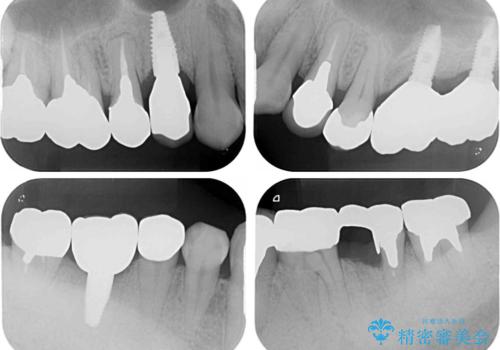

折れてしまった奥歯 インプラントによる補綴治療

左上の奥歯は2本抜歯が必要であったため、治療期間中は右側に負担がかかり、頻繁に仮歯が壊れてしまいました。

左上に仮歯が装着されたからは咬み合わせが安定し、スムーズに治療を進めることができました。